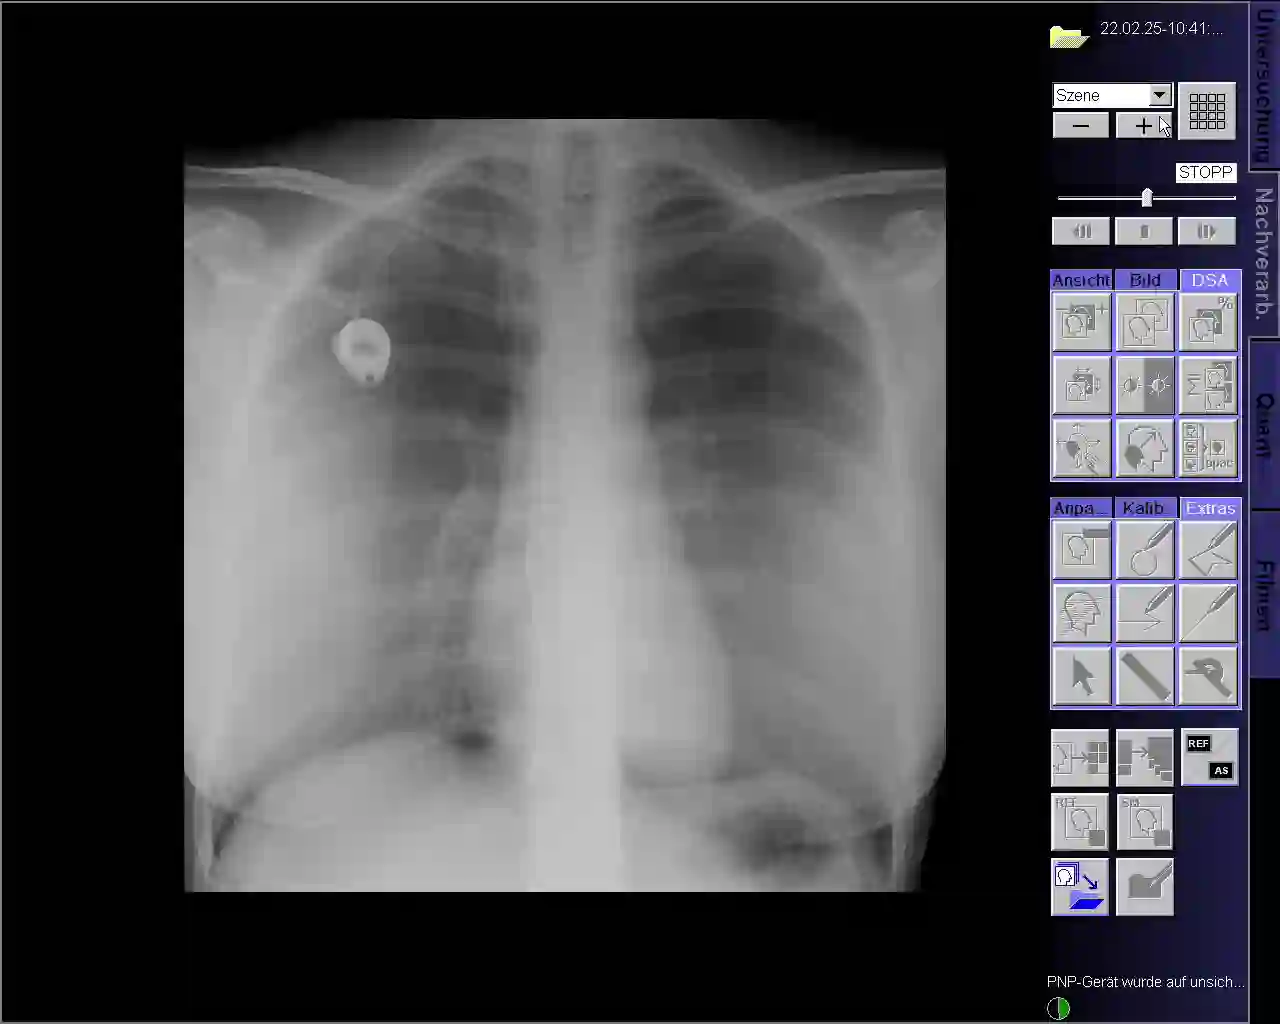

This paper presents a new multimodal interventional radiology dataset, called PoCaP (Port Catheter Placement) Corpus. This corpus consists of speech and audio signals in German, X-ray images, and system commands collected from 31 PoCaP interventions by six surgeons with average duration of 81.4 $\pm$ 41.0 minutes. The corpus aims to provide a resource for developing a smart speech assistant in operating rooms. In particular, it may be used to develop a speech controlled system that enables surgeons to control the operation parameters such as C-arm movements and table positions. In order to record the dataset, we acquired consent by the institutional review board and workers council in the University Hospital Erlangen and by the patients for data privacy. We describe the recording set-up, data structure, workflow and preprocessing steps, and report the first PoCaP Corpus speech recognition analysis results with 11.52 $\%$ word error rate using pretrained models. The findings suggest that the data has the potential to build a robust command recognition system and will allow the development of a novel intervention support systems using speech and image processing in the medical domain.